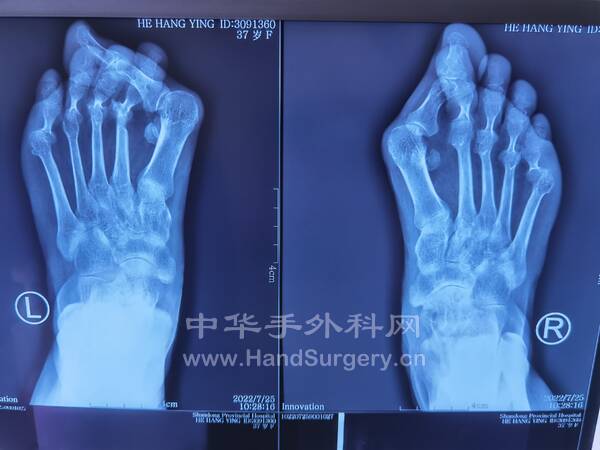

2022-7-24~7-25门诊知识点

患者女,49岁,左足不适数年,诊断为Freiberg病(4期),拟手术方案:关节清理术+闭合楔形跖骨截骨术,如果软骨面破坏严重,单纯做关节清理术(11)